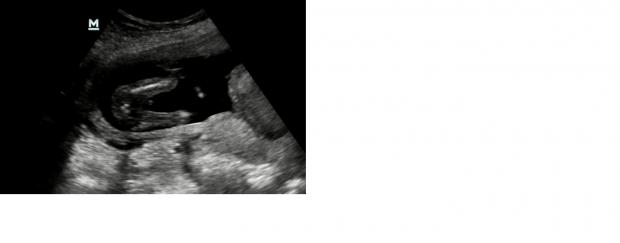

I share three pictures and a video. The video is filmed from the underside of the baby.

I would say a beautifull baby boy!

Looks like a boy

Looks boy to me

baby boy!

Does look like a boy!

Boy

First one is definitely boy